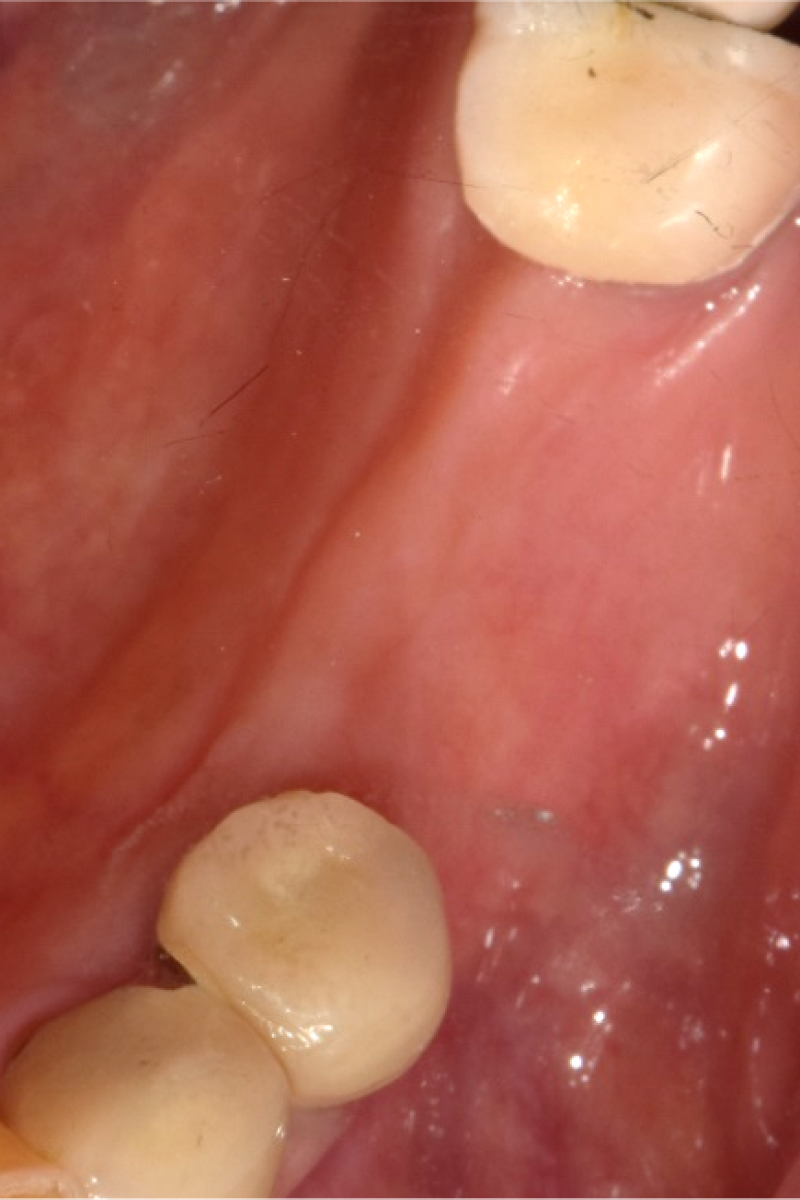

즉시 식립 임플란트 전후 사례

• 식립 전

식립 후